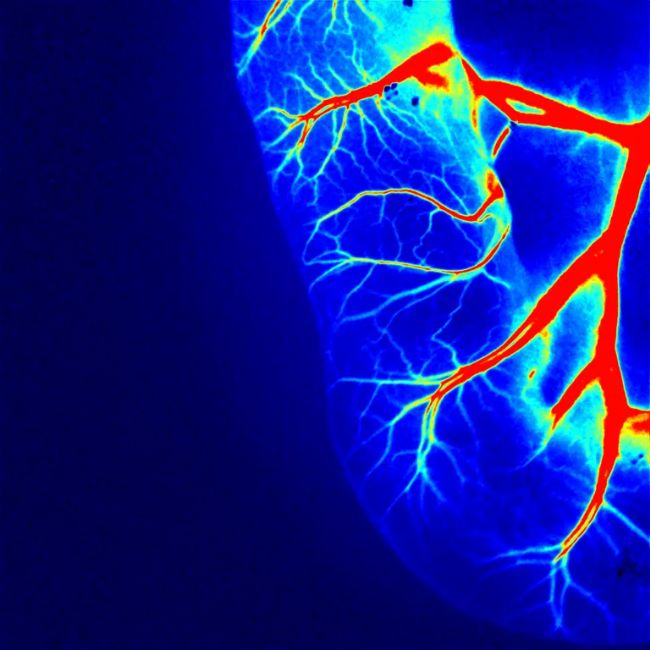

10、雞胚尿囊膜微血管

▲13日齡雞胚絨毛尿囊膜血管

在雞胚胎發(fā)育過程中,CAM 是由尿囊的中胚層與絨毛膜的中胚層融合形成的。它是一種高度血管化、無神經(jīng)支配的胚胎外膜,使其成為研究血管生成和腫瘤生長的理想基礎(chǔ)模型。

對于血管再生研究,可以局部遞送各種生物分子和藥物并研究它們的血管生成效果。對于癌癥模型,可以將各種類型的細胞移植到 CAM 中以促進腫瘤生長。這為研究許多不同的癌癥腫瘤形成提供了一個相對簡單的模型,并可進一步評估新的治療藥物和治療方式。